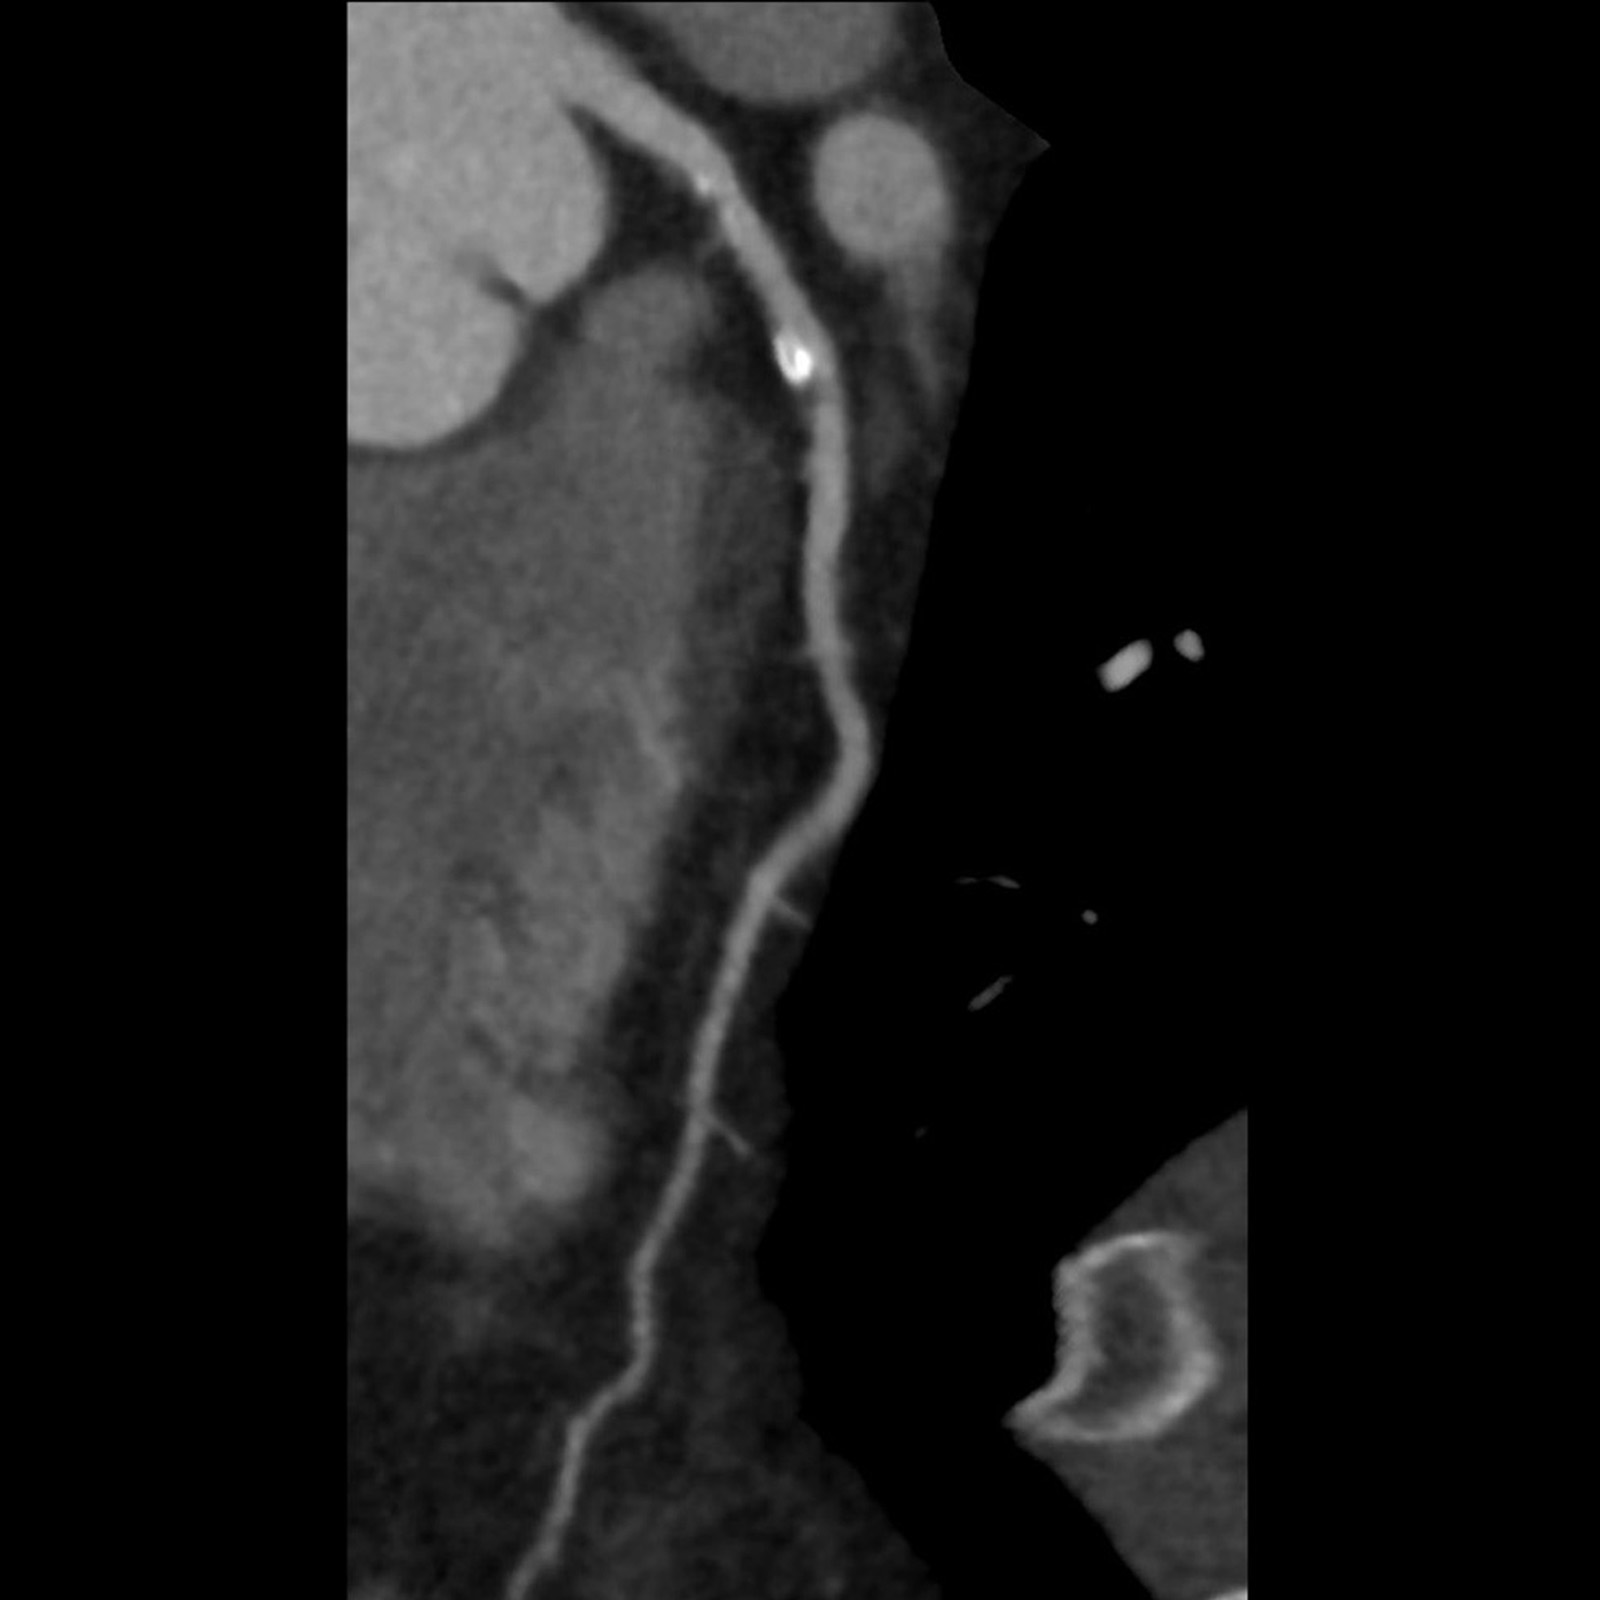

Precise IQ Engine (PIQE) 10241 DLR

Aquilion Serve SP

Improve your diagnostic confidence with PIQE 10241 to reduce cardiac blooming artifacts from calcifications with improved spatial resolution.

View Scan Parameters| Scan Mode | kVp | mAs | Reconstruction | CTDIvol | DLP | Effective Dose† |

|---|---|---|---|---|---|---|

| Helical | 100 kV | SUREExposure | PIQE | 10.6 mGy | 152.5 mGy·cm | 2.1 mSv |

† AAPM Report 96, k-factor 0.014

1 Option

Courtesy of Steinberg Diagnostic Medical Imaging, USA.